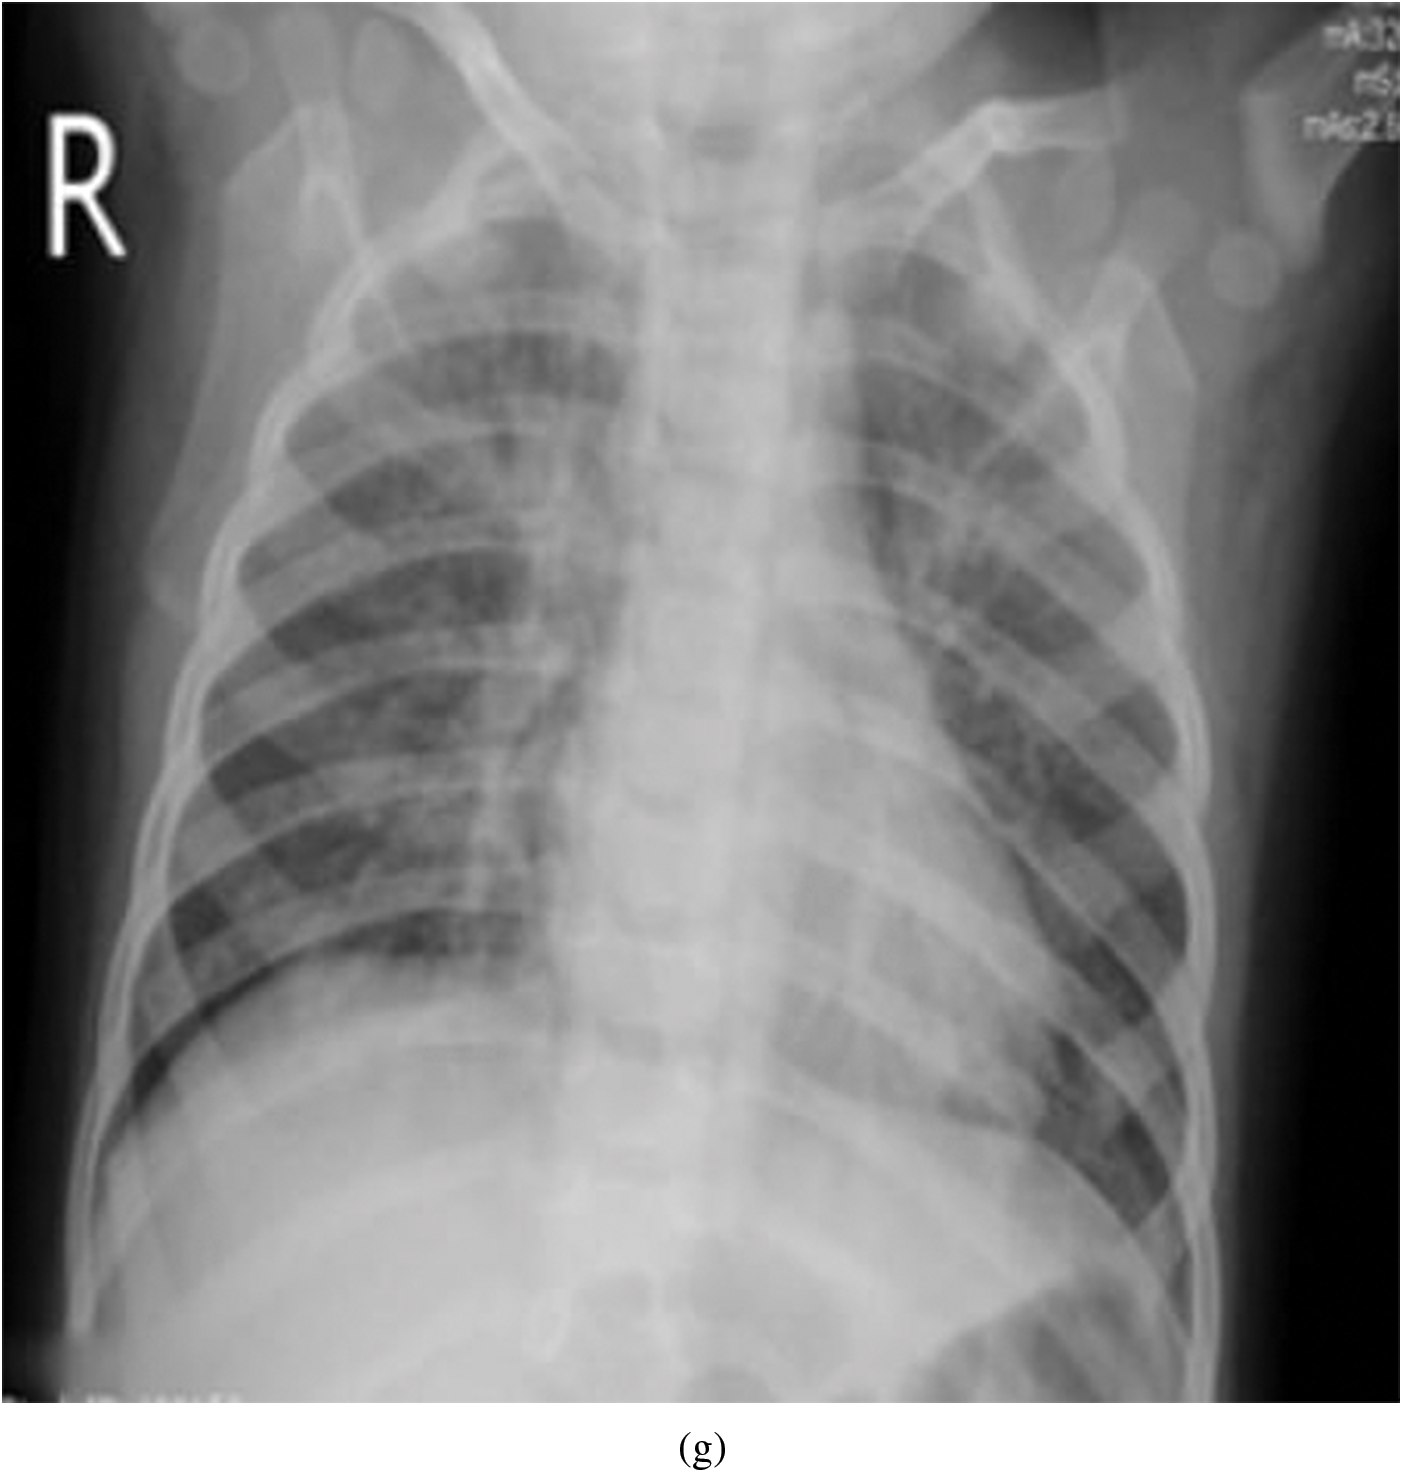

Representative images belonging to the normal, COVID-19, LO, and VP groups are shown in Figs. 2–5, along with their corresponding histograms. The images clearly depict variability in pixel intensities, particularly in and around the lung regions. The visibility of the rib cages is very obvious in the case of the normal and COVID-19 images as shown in Figs. 2a, 2b, 3a and 3b respectively compared to the LO and VP images in Fig. 4a, 4b, 5a and 5b. The visibility of lungs in COVID-19 patients is unclear. The histograms represent different perspectives, with varying distribution of intensities across the four categories, particularly COVID-19, indicating a large presence of high pixel intensities.

Figure 5: Representative image and its corresponding histogram depicting the distribution of pixel intensities of a Viral Pneumonia (VP) image